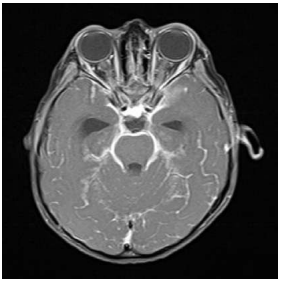

Um homem de 29 anos de idade e recém-diagnosticado

com HIV (CD4 25) apresentou-se com febre, dor de

cabeça e fotofobia. A análise de LCR evidenciou pleocitose

linfocítica, aumento de proteínas e glicose consumida. A

RNM de crânio apontou realce leptomeningeo das cisternas

da base.

A partir desse caso clínico hipotético, assinale a opção com a hipótese diagnóstica adequada.